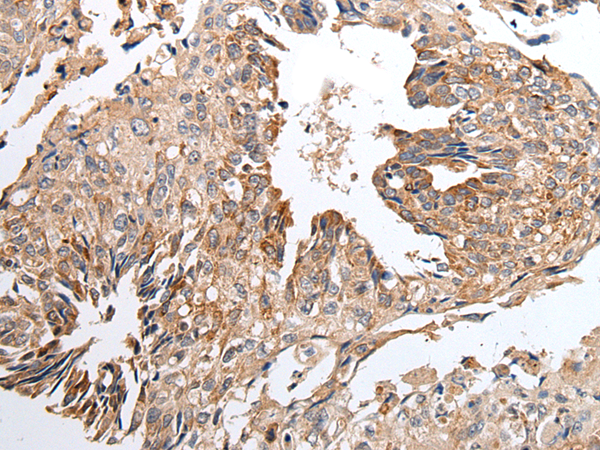

IHC positive control: |

Human lung cancer and human breast cancer |

IHC Recommend dilution: |

25-100 |